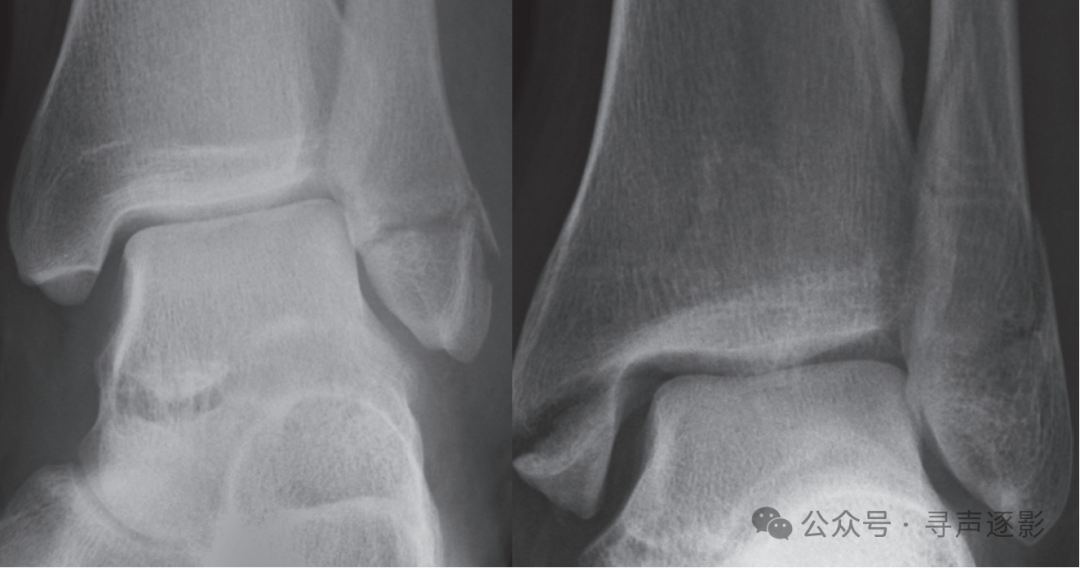

左图:外踝横形骨折。右图:内踝横形骨折;腓骨远端及外踝斜形与横形骨折;距骨外侧半脱位。

左图:胫骨与腓骨多处骨折。右图:注意胫腓关节间隙明显增宽,提示骨间膜断裂。距骨外侧突可见小碎骨片(箭头所示),提示韧带损伤。

在实际工作中,必须将前后位片与侧位片视为一组,一并评估。该患者的前后位片显示外踝横形骨折及距骨外侧半脱位;侧位片则清晰呈现腓骨骨折的全长及移位程度,并可同时评估后踝、距骨及跟骨的情况。